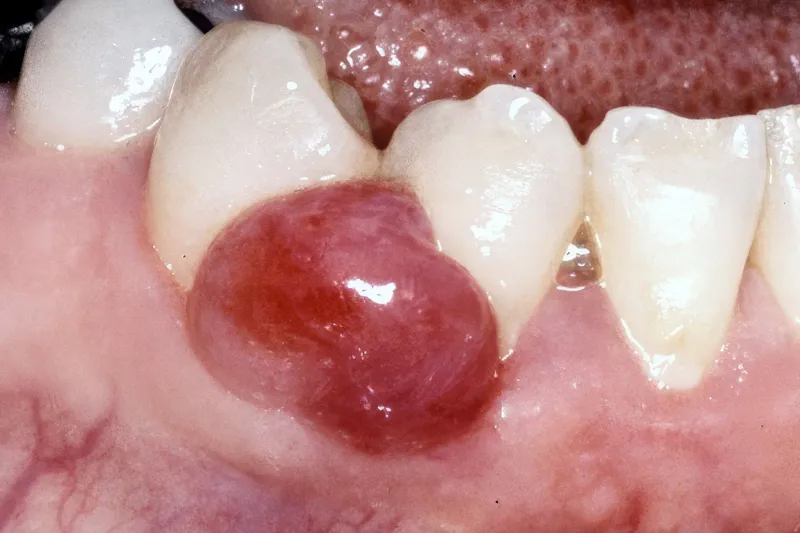

Hævelser i mundslimhinden kan opstå som følge af en væskeansamling (fx spyt, pus og ødem) eller en vævsforøgelse. Vævsforøgelser kan være non-neoplastiske eller neoplastiske. De non-neoplastiske vævsforøgelser er hyppigst forekommende og er ofte reaktive, irritationsbetingede hyperplasier (fx det pyogene granulom eller den fokale fibrøse hyperplasi). De kan også være relateret til generelle sygdomme, medicinindtagelse eller være udviklingsbetingede. Infektion med humant papillomvirus kan resultere i udvikling af papillomer, og mucocele kan opstå som følge af traumatiseret spytkirtelvæv. Ved bl.a. morbus Crohn kan ses hævelser i form af mukosale hyperplasier/folder med granulomatøs inflammation. Gingivale hyperplasier er de mest almindelige medicininducerede hævelser. De neoplastiske vævsforøgelser er karakteriserede ved abnorm og ukontrolleret cellevækst og kan være benigne eller maligne tumorer. Såvel de benigne (fx fibrom) som maligne (fx fibrosarkom) neoplasier forekommer sjældnere, men udgør væsentlige differentialdiagnoser. Det kan undertiden være vanskeligt klinisk at adskille reaktive hyperplasier fra egentlige neoplasier. Det exciderede væv skal derfor altid undersøges histologisk for endelig verifikation af diagnosen. De forskellige mundslimhindetumorer kan også være vanskelige at adskille klinisk. En biopsi vil således være påkrævet og selvsagt afgørende for den videre behandling. Det er vigtigt for tandlæger at have kendskab til de forskellige typer af mundslimhindehævelser for at kunne stille relevante kliniske tentative diagnoser og vide, hvornår der er grundlag for biopsi og videre henvisning til specialtandlæge eller speciallæge. I nærværende artikel gennemgås de mest almindelige mundslimhindehævelser og relevante differentialdiagnostiske overvejelser.

Non-neoplastiske reaktive blødtvævshævelser forekommer relativt hyppigt i mundhulen. I nogle tilfælde kan de være vanskelige at adskille fra egentlige blødtvævstumorer (neoplasier). Det er derfor vigtigt for tandlæger at have kendskab til de forskellige typer af bløddelshævelser, herunder deres kliniske karakteristika, for at kunne stille relevante kliniske tentative diagnoser og vide, hvornår der er grundlag for biopsi og videre henvisning til specialtandlæge eller speciallæge.